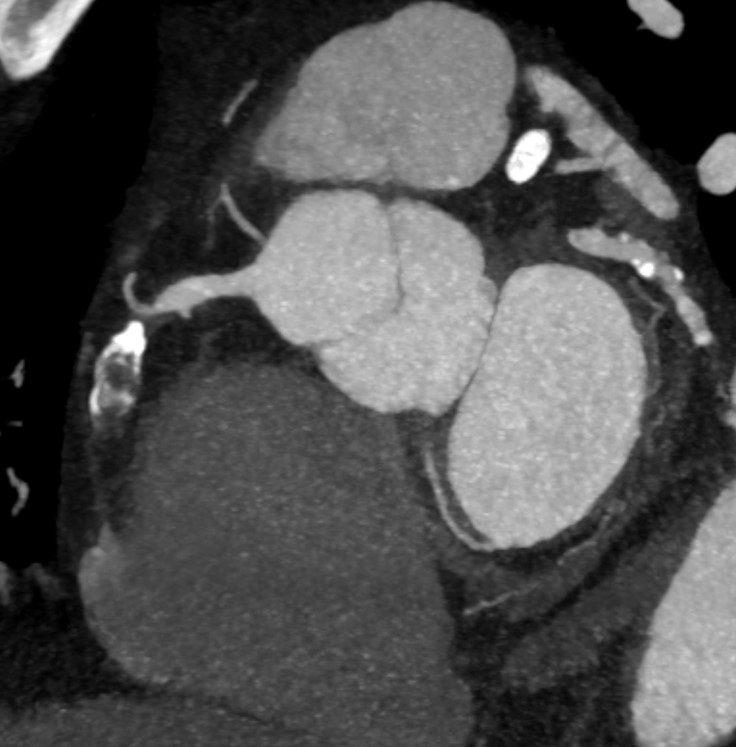

Echocardiography demonstrated a normal left ventricular ejection fraction but revealed akinesia of the basal septum and inferior wall. Myocardial SPECT showed a large, reversible perfusion defect in the inferior wall with an ischemia extent of 4%. Pre-procedural CT angiography identified a complex RCA CTO characterized by a severe calcified nodule at the proximal segment, predicting high difficulty for device crossing.

Diagnostic coronary angiography revealed a very long (>40mm) chronic total occlusion of the RCA with a J-CTO score >3. The lesion presented with ambiguous caps at both the proximal entry and distal exit points. Well-developed septal collaterals supplying the posterior descending artery (PDA) were present (CC score 3). The distal vessel architecture was further complicated by in-stent restenosis (ISR) from the previous stent implantation.

The procedure began with an antegrade attempt using a Sion wire in Corsair Pro, which failed due to the ambiguous proximal cap. We promptly switched to a retrograde approach via the septal channels. A SUOH 03 wire successfully surfed the collaterals to the distal RCA but was unable to penetrate the distal ISR segment. To bypass this barrier, we escalated to a Gladius polymer wire, which passed the ISR but tracked into the false lumen, causing a retrograde dissection. We exchanged for a Gaia Next 2 wire and carefully redirected the tip to puncture back into the true lumen near the proximal cap. Despite successful wiring, the retrograde microcatheter could not cross the calcified proximal cap to allow for externalization. To resolve this, we employed the "Tip-In" technique: an antegrade microcatheter was advanced to the tip of the retrograde wire inside the guiding catheter, and the retrograde wire was steered into the antegrade catheter to secure the rail. Following this, we exchanged for a Rota wire. Rotational Atherectomy with a 1.25mm burr was performed to modify the severe proximal calcified nodule that had prevented microcatheter passage. After IVUS-confirmed plaque modification, we implanted two overlapping Xience Skypoint stents (4.0 x 48 mm) and performed high-pressure post-dilatation with a 4.5mm non-compliant balloon.